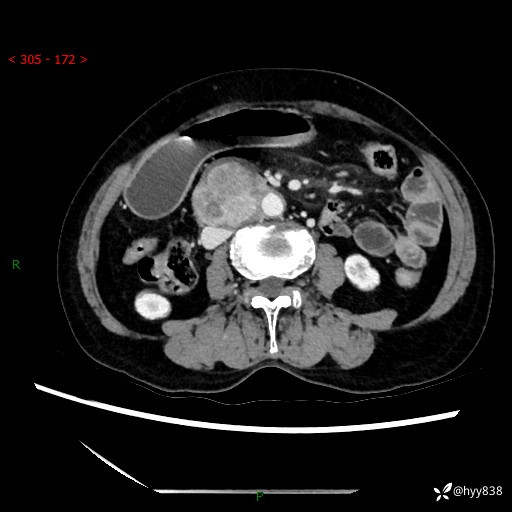

71岁/女,腹痛1月余。腹膜后肿物,间质瘤 VS 副节瘤 VS 平滑肌肉瘤---(有结果)

【患者信息】:71岁/女

【主诉】:腹痛1月余

【现病史及既往史】:患者于1月前无明显诱因出现右下腹部疼痛不适,呈阵发性隐痛,尚可耐受,放射至后背部及腰部疼痛,伴排便困难,不伴其它部位疼痛,无嗳气,无不洁饮食,无黑便,无恶心、呕吐、腹胀腹泻、呕血、发热、寒颤、厌油、黄疸,多次就诊于当地区太湖医院拍片示: 行抗炎等对症支持治疗,效果尚可。现患者上述不适症状明显进一步加重,为求进一步治疗遂来我院门诊就诊,门诊以“十二指肠肿瘤?”收住我科。 起病以来,精神、睡眠可,食欲可,大便异常、小便正常,体力、体重无明显下降。

【检查】:腹部CT增强扫描(外院CT平扫)